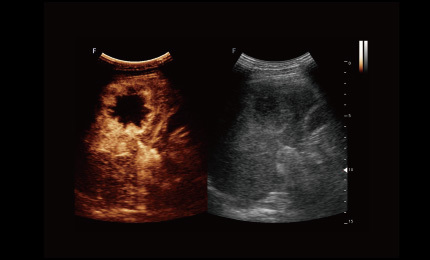

Obrazowanie kontrastowe

Technologia obrazowania ultrasonograficznego z inwersją impulsów i kontrastowaniem pozwala dokładnie wyodrębnić drugi harmoniczny kontrastowych mikropęcherzyków, co umożliwia uzyskanie obrazowania z wysokim stosunkiem kontrastu do tkanki oraz zapewnia bardziej szczegółową diagnozę kliniczną.